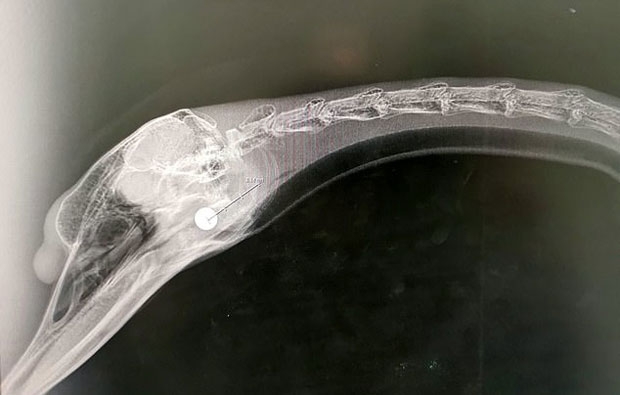

알을 품고 있다 습격을 받은 어미 백조는 머리에 총을 맞고도 둥지를 지킨 것으로 알려졌다. 피범벅이 된 백조는 지난 23일 머리에 박힌 8㎜짜리 총탄을 제거하는 수술을 받고 치료 중이며, 백조 알 4구는 모처로 옮겨졌다.